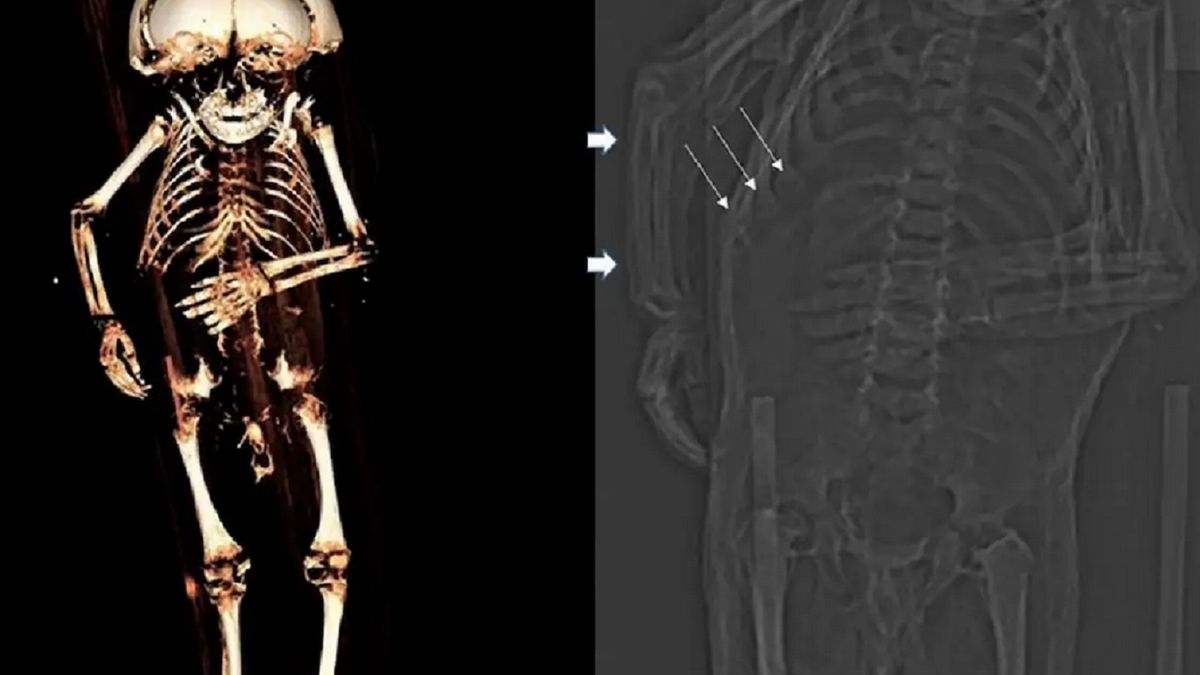

Naukowcy przeprowadzili kompleksowe badania zmumifikowanych zwłok, które znaleziono w krypcie austriackich arystokratów. Ciało należało do zaledwie rocznego chłopca. Miał on nadwagę oraz niedobór witaminy D, spowodowany brakiem ekspozycji na światło słoneczne.

Zmumifikowane zwłoki dziecka zostały znalezione w krypcie hrabiów Starhemberg w Austrii. Chociaż historycy od dawna podejrzewali, że mogą należeć do któregoś z potomków książęcej rodziny, to dopiero teraz uzyskali pewność. Badania wykazały także zaskakująca przyczynę śmierci malca. To skrajny niedobór witaminy D, związany z brakiem dostępu do światła słonecznego.

Wyniki "wirtualnej sekcji zwłok" opublikowano 25 października w czasopiśmie "Frontiers in Medicine". Zespół badaczy z Kliniki Akademickiej Monachium-Bogenhausen wykorzystał tomografię komputerową, zapisy rodzinne, testy radiowęglowe i inne wskazówki dotyczące pochówku.

Ustalono, że zwłoki należą do Reicharda Wilhelma, wnuka hrabiego Reicharda von Starhemberga. Chłopiec żył w epoce renesansu, między XVI a XVII wiekiem. W chwili śmierci miał od 10 do 18 miesięcy. Został pochowany w trumnie z drewna i metalu. Miał na sobie płaszcz z kapturem wykonany z jedwabiu.

Pomimo pochodzenia i bogactwa rodziny, dziecko zmarło z nietypowego powodu - "skrajnego niedoboru żywieniowego i zapalenia płuc". Badania wykazały, że w chwili śmierci chłopiec miał nadwagę. Andreas Nerlich, główny autor badania i patolog z Akademickiej Kliniki Monachium-Bogenhausen w Niemczech, stwierdził natomiast, że dziecko było karmione w nieodpowiedni sposób, co doprowadziło jednocześnie do nadwagi i skrajnego niedoboru witamin.

Kombinacja otyłości wraz z poważnym niedoborem witamin może być wyjaśniona jedynie przez ogólnie dobry stan zdrowia połączony z całkowitym brakiem ekspozycji na światło słoneczne. Musimy ponownie rozważyć warunki życia wysokich arystokratycznych niemowląt poprzednich populacji - powiedział naukowiec.